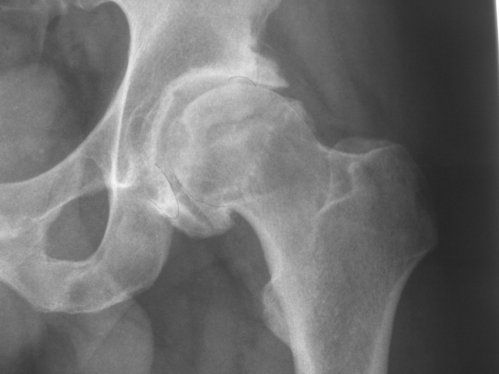

Choque femoroacetabular

ATRAPAMIENTO O CHOQUE FEMOROACETABULAR

La cadera es una articulación formada por la cabeza del fémur y el acetábulo de la pelvis. Tiene un amplio rango de movimiento que además soporta carga al caminar, correr o saltar.

Recientemente se ha descrito el Síndrome de Pinzamiento Femoroacetabular que consiste en dolor inguinal debido a alteraciones anatómicas en el cuello femoral y/o en la orientación del acetábulo, que provocan un exceso de contacto en los movimientos de la cadera, favoreciendo el desarrollo de lesiones osteocartilaginosas y capsulolabrales.